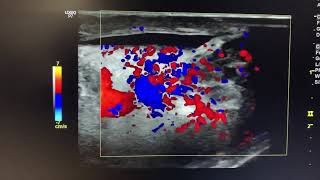

Orchiditis

0:31 Testis İltihabının (Orşit) Belirtileri Nelerdir?   Testis İltihabının (Orşit) Belirtileri Nelerdir? 0:30 Testis İltihabı (Orşit) Nasıl Tedavi Edilir?   Testis İltihabı (Orşit) Nasıl Tedavi Edilir? 8:05 Understanding Epididymo-orchitis   Understanding Epididymo-orchitis 0:47 Testis İltihabı (Orşit) Ne Gibi Sorunlara Yol Açabilir?   Testis İltihabı (Orşit) Ne Gibi Sorunlara Yol Açabilir? 1:39 Testis ağrıları (Epididimit - Orşit) nedir? Tanı ve tedavisi nasıldır?   Testis ağrıları (Epididimit - Orşit) nedir? Tanı ve tedavisi nasıldır? 5:35 Orchitis / Inflammation of the Testicles | Causes & Treatment | Dr Neel Patel   Orchitis / Inflammation of the Testicles | Causes & Treatment | Dr Neel Patel 2:35 Orşit Nedir? | Kedi ve Köpeklerde Testis İltihabıyla Nasıl Başa Çıkılır?   Orşit Nedir? | Kedi ve Köpeklerde Testis İltihabıyla Nasıl Başa Çıkılır? 4:19 Orşit / Epididimoorşit Nedir? Nasıl Tedavi Edilir?   Orşit / Epididimoorşit Nedir? Nasıl Tedavi Edilir? 0:50 Testis İltihabı (Orşit) Nedir?   Testis İltihabı (Orşit) Nedir? 0:34 Testis Ağrıları Hangi Hastalıkların Habercisi Olabilir?   Testis Ağrıları Hangi Hastalıkların Habercisi Olabilir? 3:51 #Orchitis: Causes, Symptoms, and Treatment for Testicular Pain   #Orchitis: Causes, Symptoms, and Treatment for Testicular Pain 0:11 Case 1: Epididymo orchitis clip 1   Case 1: Epididymo orchitis clip 1 1:02 How To Say Orchiditis   How To Say Orchiditis 3:36 Testicular Orchitis || Symptoms, Causes and treatment || Dr C Suvarchalaa || ZIVA Fertilityy   Testicular Orchitis || Symptoms, Causes and treatment || Dr C Suvarchalaa || ZIVA Fertilityy 0:11 Orchitis Ultrasound | Testis Sonography | ARDMS | Sonographer   Orchitis Ultrasound | Testis Sonography | ARDMS | Sonographer 0:24 Pediatric Scrotal ultrasound - Acute orchoepididymitis presumably secondary to hydatide torsion   Pediatric Scrotal ultrasound - Acute orchoepididymitis presumably secondary to hydatide torsion 1:41 Orchitis | painful testis in kids | Child surgeon   Orchitis | painful testis in kids | Child surgeon 0:44 ULTRASOUND acute epididymoorchitis   ULTRASOUND acute epididymoorchitis 0:46 Testis Ağrıları Nasıl Tedavi Edilir?   Testis Ağrıları Nasıl Tedavi Edilir?